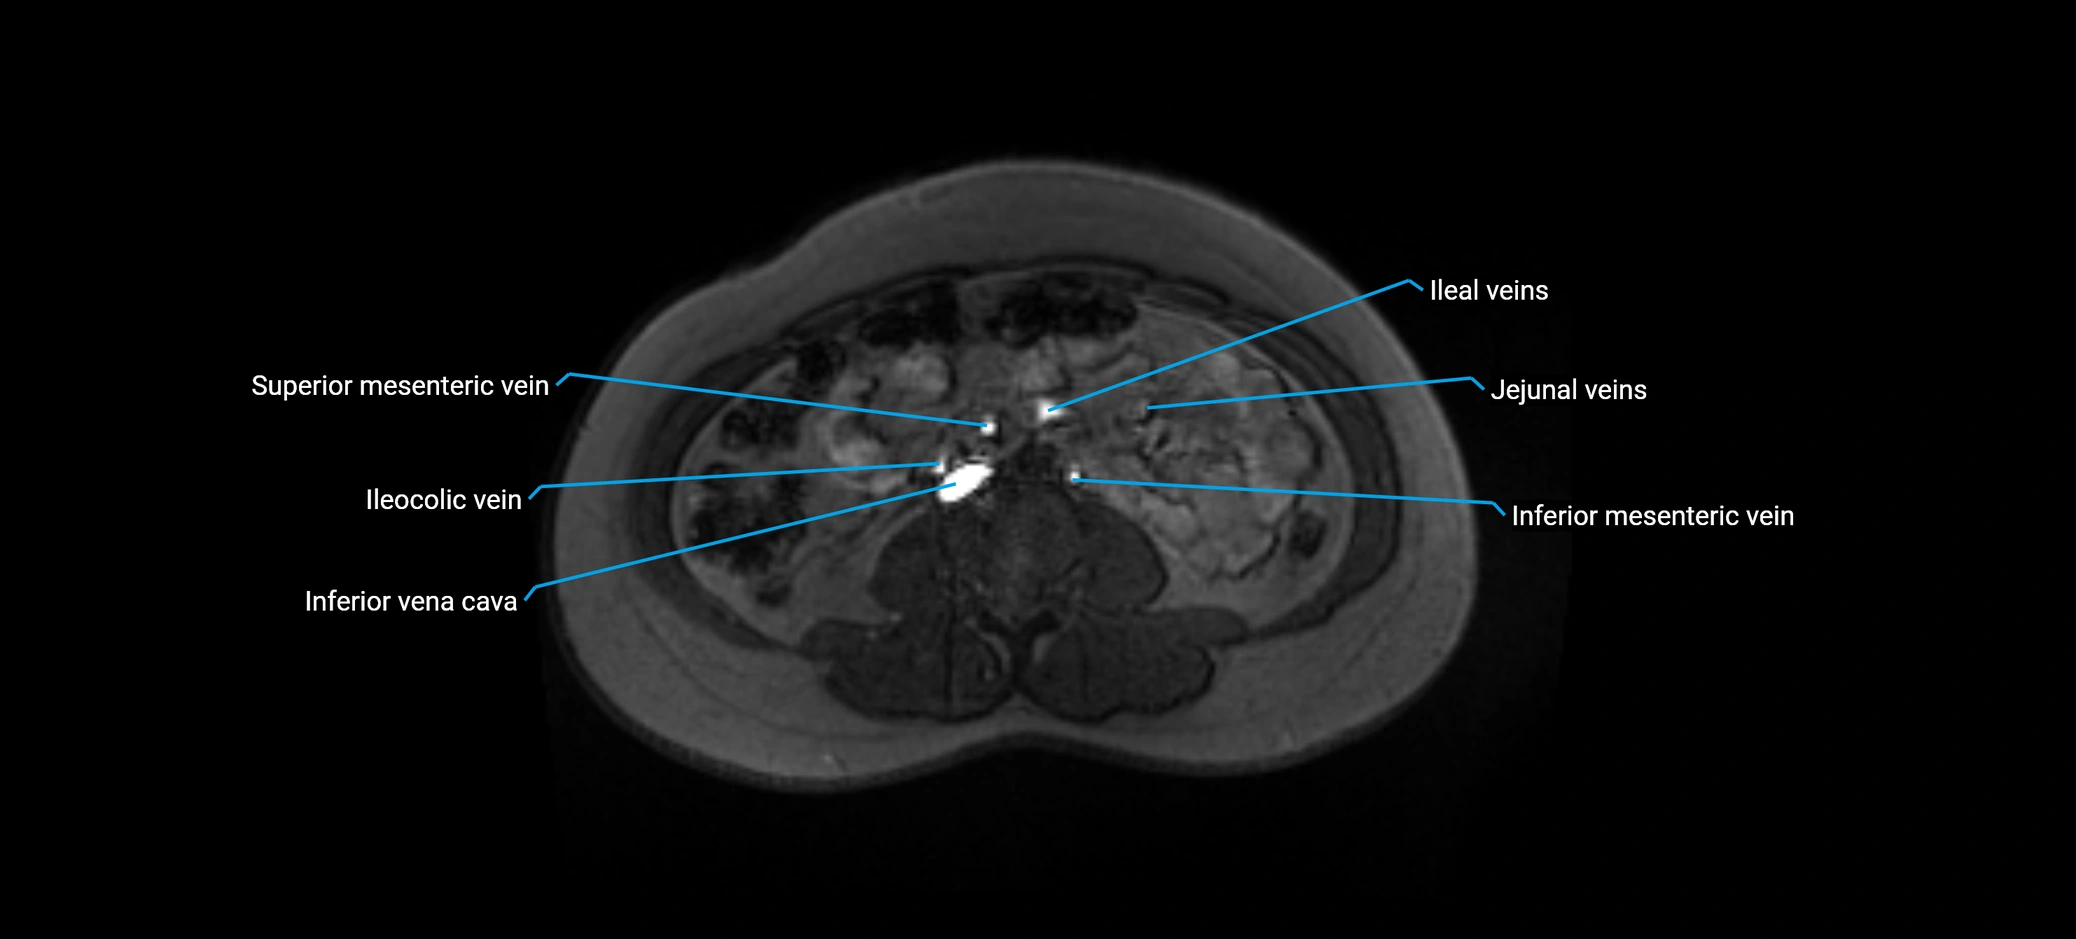

MRI image

image